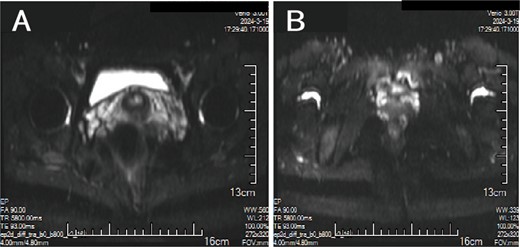

A 38-year-old married female patient presented with a lump near her anus 10 years ago, without apparent cause or symptoms such as redness, swelling, heat, or pain, nor cough, abdominal pain, or diarrhea. No specific treatment was administered. The patient now reports that the lump has grown larger and is accompanied by increasing swelling and discomfort. Seeking further diagnosis and treatment, she visited our outpatient department, where she was admitted with the condition “perianal lump.” Physical examination revealed a body temperature of 36.5°C, pulse rate of 86 beats/min, respiratory rate of 19 beats/min, and a blood pressure of 134/85 mmHg. Admission symptoms include perianal swelling and pain, with itching; no signs of fever, chills, rupture, or pus discharge; bowel movements once or twice daily, and normal urination. The patient has one child and underwent a lateral epidural resection 12 years ago due to natural childbirth. Specialist examination revealed a 4-cm lump with a hard texture at 7–11 o’clock next to the anus, and a radial surgical incision at the 7 o’clock anal margin. Digital rectal examination found no lump, depression, or induration in the anus, and no blood on fingertips. The initial diagnosis was a perianal lump. Auxiliary examinations included ultrasound, which revealed a 4-cm lump in the subcutaneous soft tissue near the anus with minor blood flow signals within and around it, suggestive of an inflammatory lesion (Fig. 1A and B); and pelvic MRI, which suggested a left perianal lump consistent with a perianal abscess (Fig. 2A and B). Under spinal anesthesia, the perianal lump was removed, and postoperative pathology confirmed the presence of endometriosis (Fig. 3).

Ultrasound: (A) 2D ultrasound shows a mixed echo with a range of about 4 cm in the subcutaneous soft tissue around the left side of the anus, presenting as cystic-solid; (B) color doppler shows a small amount of punctate blood flow signal inside and around the mixed echo.